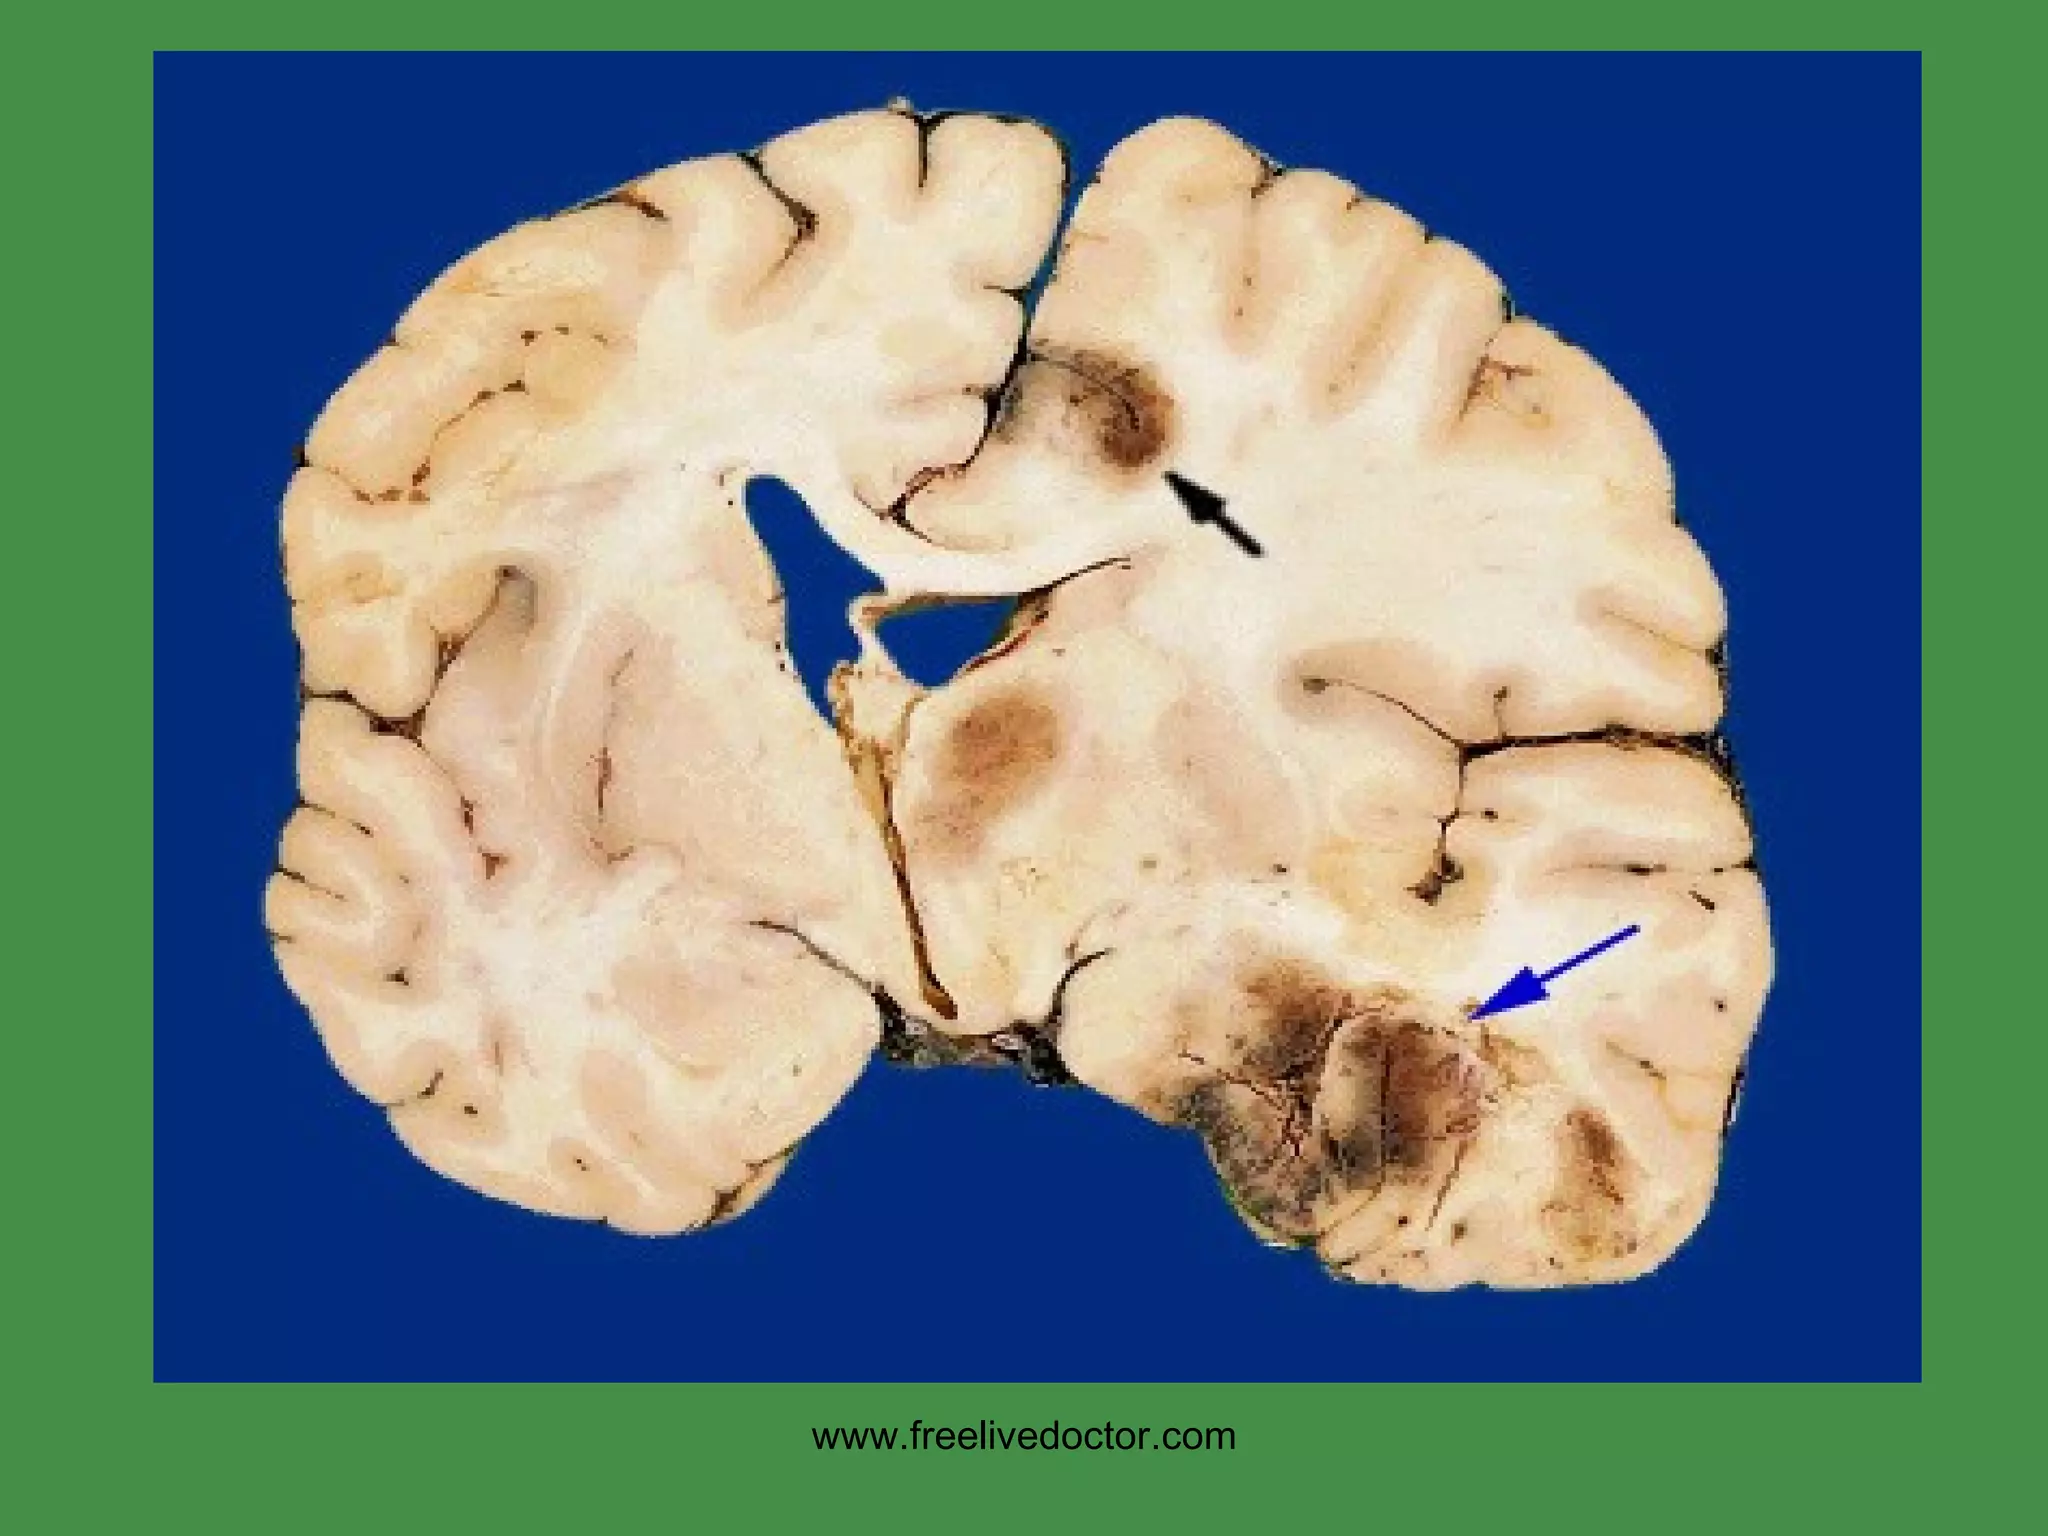

HSV = TEMPORAL lobe(s) www.freelivedoctor.com

Bitemporal encephalitis is HSV until proven otherwise! www.freelivedoctor.com